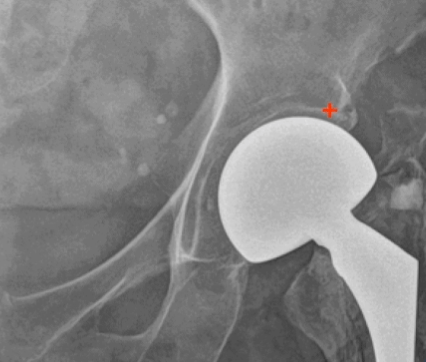

초기 치환술 후 5년이 지나면서 관절이 뼈 속으로 내려앉는 침강 현상이 나타날 수 있습니다.

이로 인해 다리 길이가 3~4cm 정도 짧아지면서 절뚝거리는 보행 장애가 발생하게 됩니다.

70대 여성 환자분의 사례를 보면, 50대에 낙상으로 인한 골절로 부분 치환술을 받으신 후 처음에는 좋은 경과를 보였습니다.

하지만 5년 후 관절이 침강하면서 다리 길이가 약 4cm 짧아져 첫 번째 재치환술이 필요했습니다.